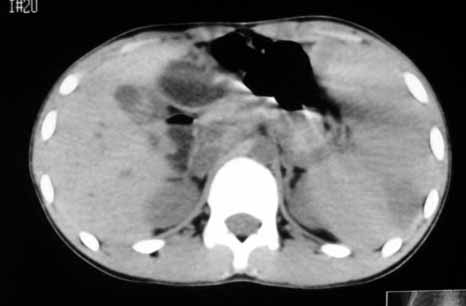

以下是引用zhangzhongshou在2007-5-22 21:04:00的发言:[br]1、脾肿大[br]2、脾脏低密度影,血管瘤?脾梗塞不能除外,建议增强扫描。

以下是引用dyqct在2007-5-22 20:45:00的发言:[br]巨脾,可疑梗塞,建议增强、查血象进一步检查

以下是引用liuyue在2007-5-23 7:57:00的发言:[br]腹主动脉周多个肿大淋巴结,脾大伴三角形低密度影,肠腔积气,考虑:1淋巴瘤2脾大伴梗塞3肠腔积气(肿大淋巴结压迫所致)